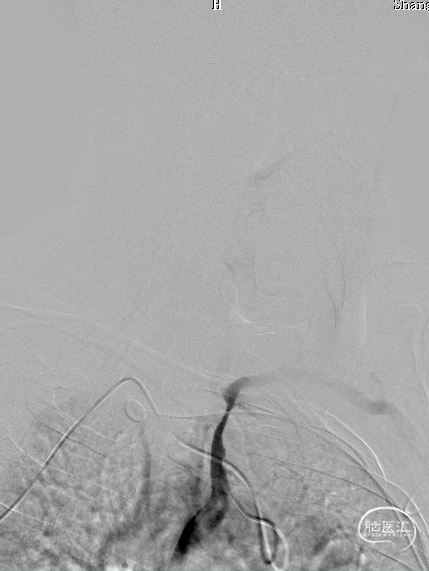

DSA:L-CCA。

患者出现意识模糊、呕吐、胸闷等不适,查体:血压升高(血压200/100mmHg),神清,对答切题,伸舌居中,查体部分配合,四肢肌力5级,双眼向右凝视伴水平眼震。

立即行Dyna-CT,未见脑出血表现,立即予以尼卡地平及尼莫地平降压,动脉静推负荷量替罗非班。

造影见LV闭塞,立即沿0.014*200cm 通桥北斗SS™神经血管导丝置入3mm*16mm 药物球扩支架至LV1。

压力泵逐渐加压球扩支架到8atm, 支架打开良好,造影示残余狭窄0%。